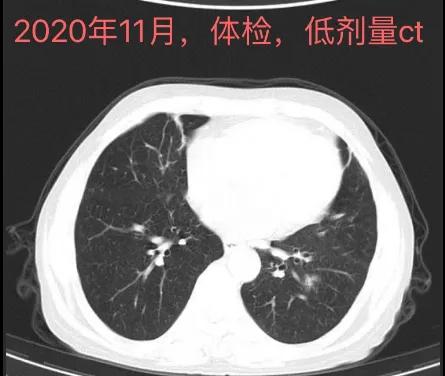

戴主任,您好!我爸爸情况,男,67岁,吸烟多年。2020年11月体检第一次提示结节(体检之前持续咳嗽2个月左右,未做抗炎治疗),大小17*13(2018年7月体检时没有)。2022年5月再次体检时,报大小15*11(后来请医生再次看过应该是测量误差)。之后马上做了增强CT,图片都附在下面。不知道您是否能看得清楚,拜请您百忙之中帮我看看我爸爸这个结节,是不是尽快要手术了?大概是什么性质了呢?手术可以微创吗?(这边胸外科医生说纵隔窗淋巴结稍大,怕影响微创操作)手术的话是要叶切吗?这个年龄预后会怎么样呀?自从复查以来我真的没有一天不焦虑,满脑子都是这个事情。麻烦您了,非常感谢您!也祝您工作顺利,生活愉快!

今年五一假期,我带着父母去做年度体检,看见爸爸走进CT室时我就非常紧张(前一天晚上我仔细阅读上年度体检报告时才发现报告上提示肺结节1.7cm。因为某些原因,去年体检报告我没有仔细看,也因为没有相关方面知识,我爸自己也没有当回事。我非常的自责和内疚,只能不停的在心中祈祷)。爸爸做完CT我马上就去问了医生,她表示结节还在,但好在大小较去年没有变化,建议上级医院检查。心头一紧,赶紧摸出手机,联系朋友打听专家,想办法挂号,同时拷贝了电子影像备用。